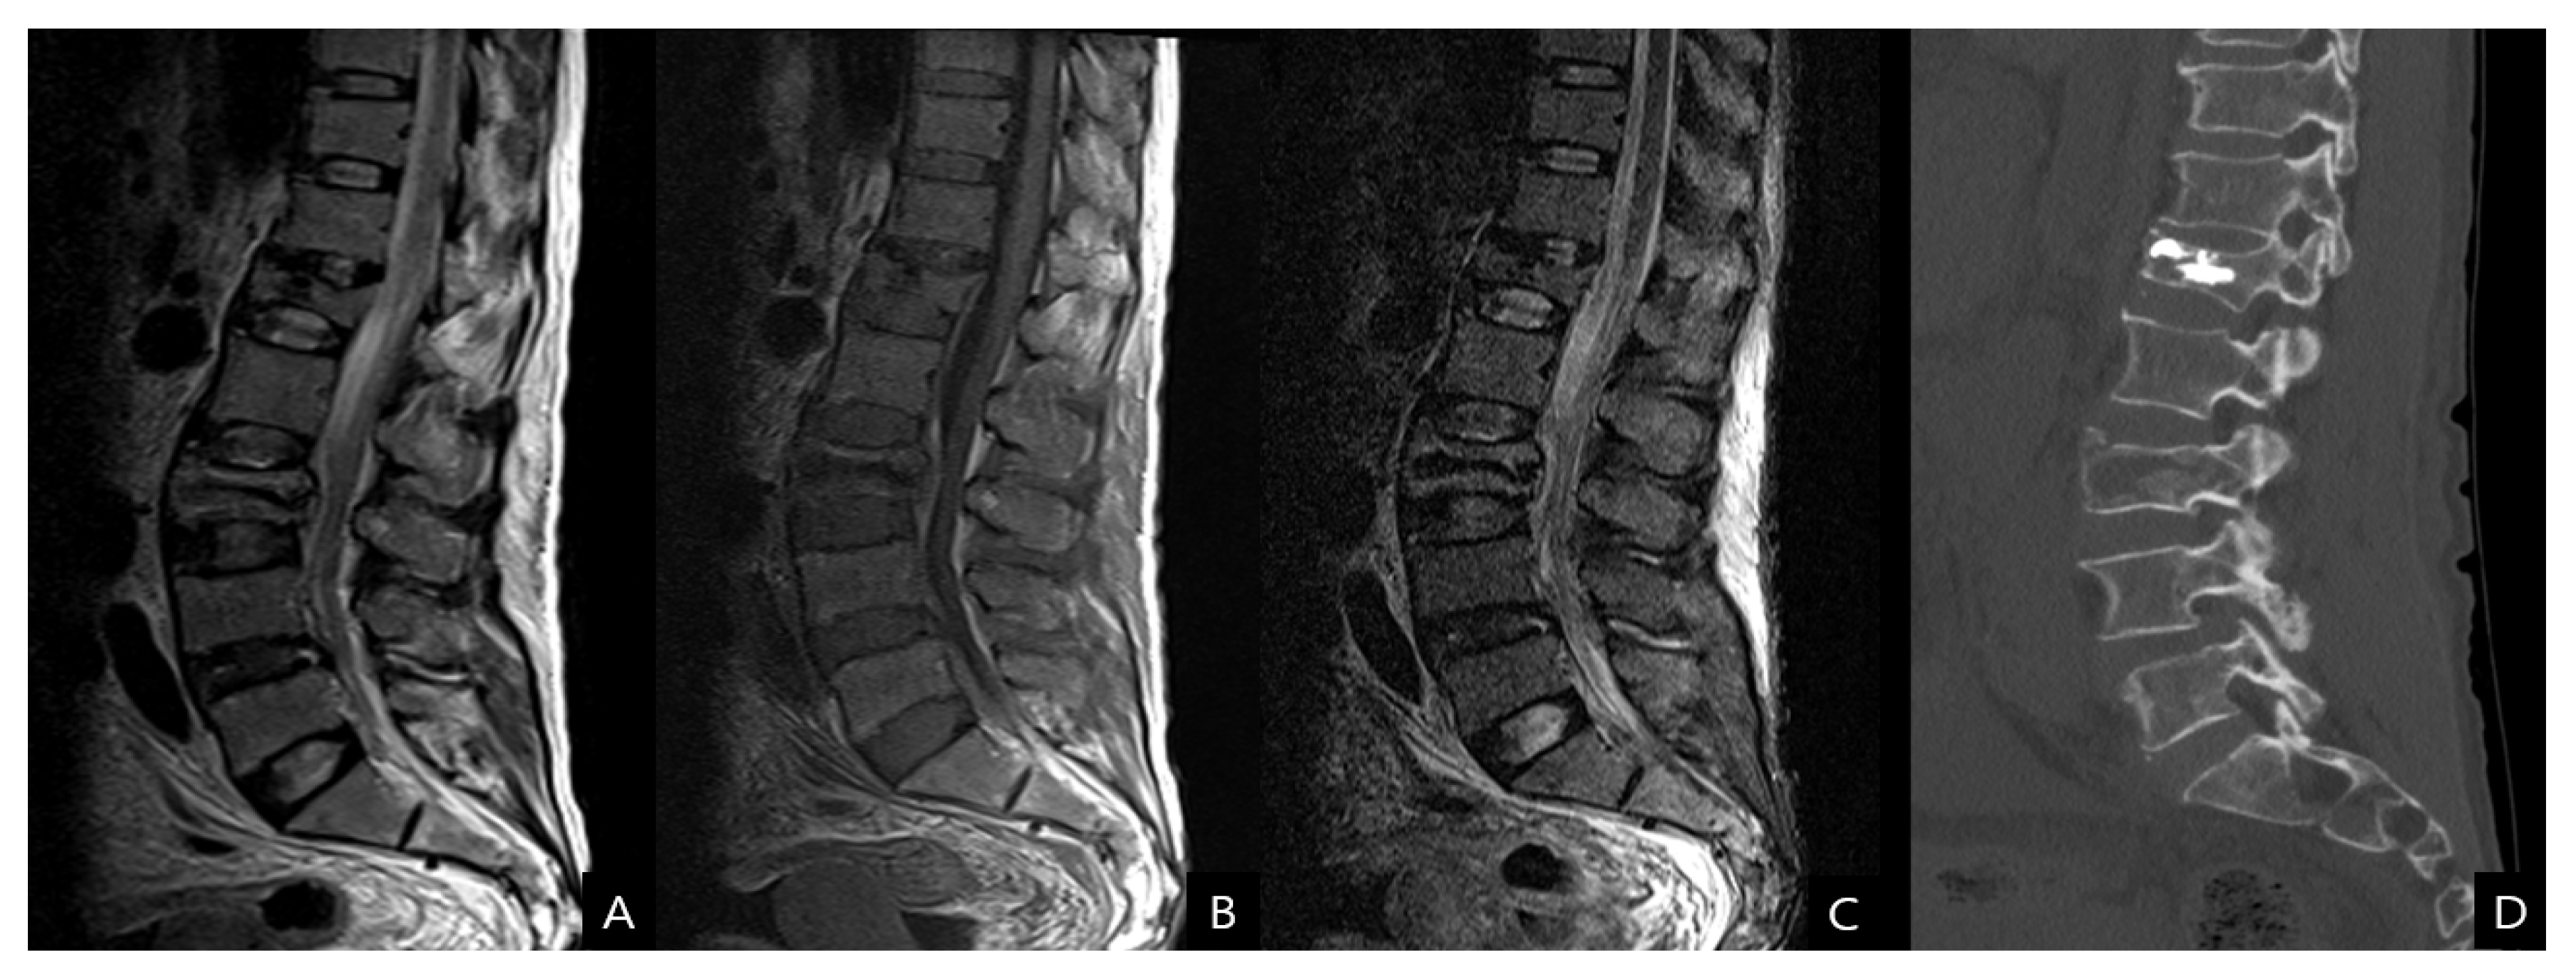

Considering the patient’s low hemoglobin level, an emergent computed tomography (CT) scan of the abdomen and lumbar spine was performed to exclude hemorrhages. Enhanced CT scans revealed a massive psoas hematoma, measuring 10 × 7 × 11 cm, extending from L2 to L5. Contrast dye leakage into the hematoma due to active bleeding from the injured segmental artery was detected (Figure 1). Magnetic resonance imaging (MRI) and CT scan of the lumbar spine revealed a stable osteoporotic VCF at L3 and an old compression fracture at L1, where vertebroplasty had already been performed (Figure 2). DEXA bone mineral densitometry was performed and showed severe osteoporosis (mean T-score of femur neck and spine: −3.6).

Figure 2.

(A) T2-weighted, (B) T1-weighted, (C) short tau inversion recovery magnetic resonance images and also (D) computed tomography scan show a stable-type osteoporotic VCF at L3.